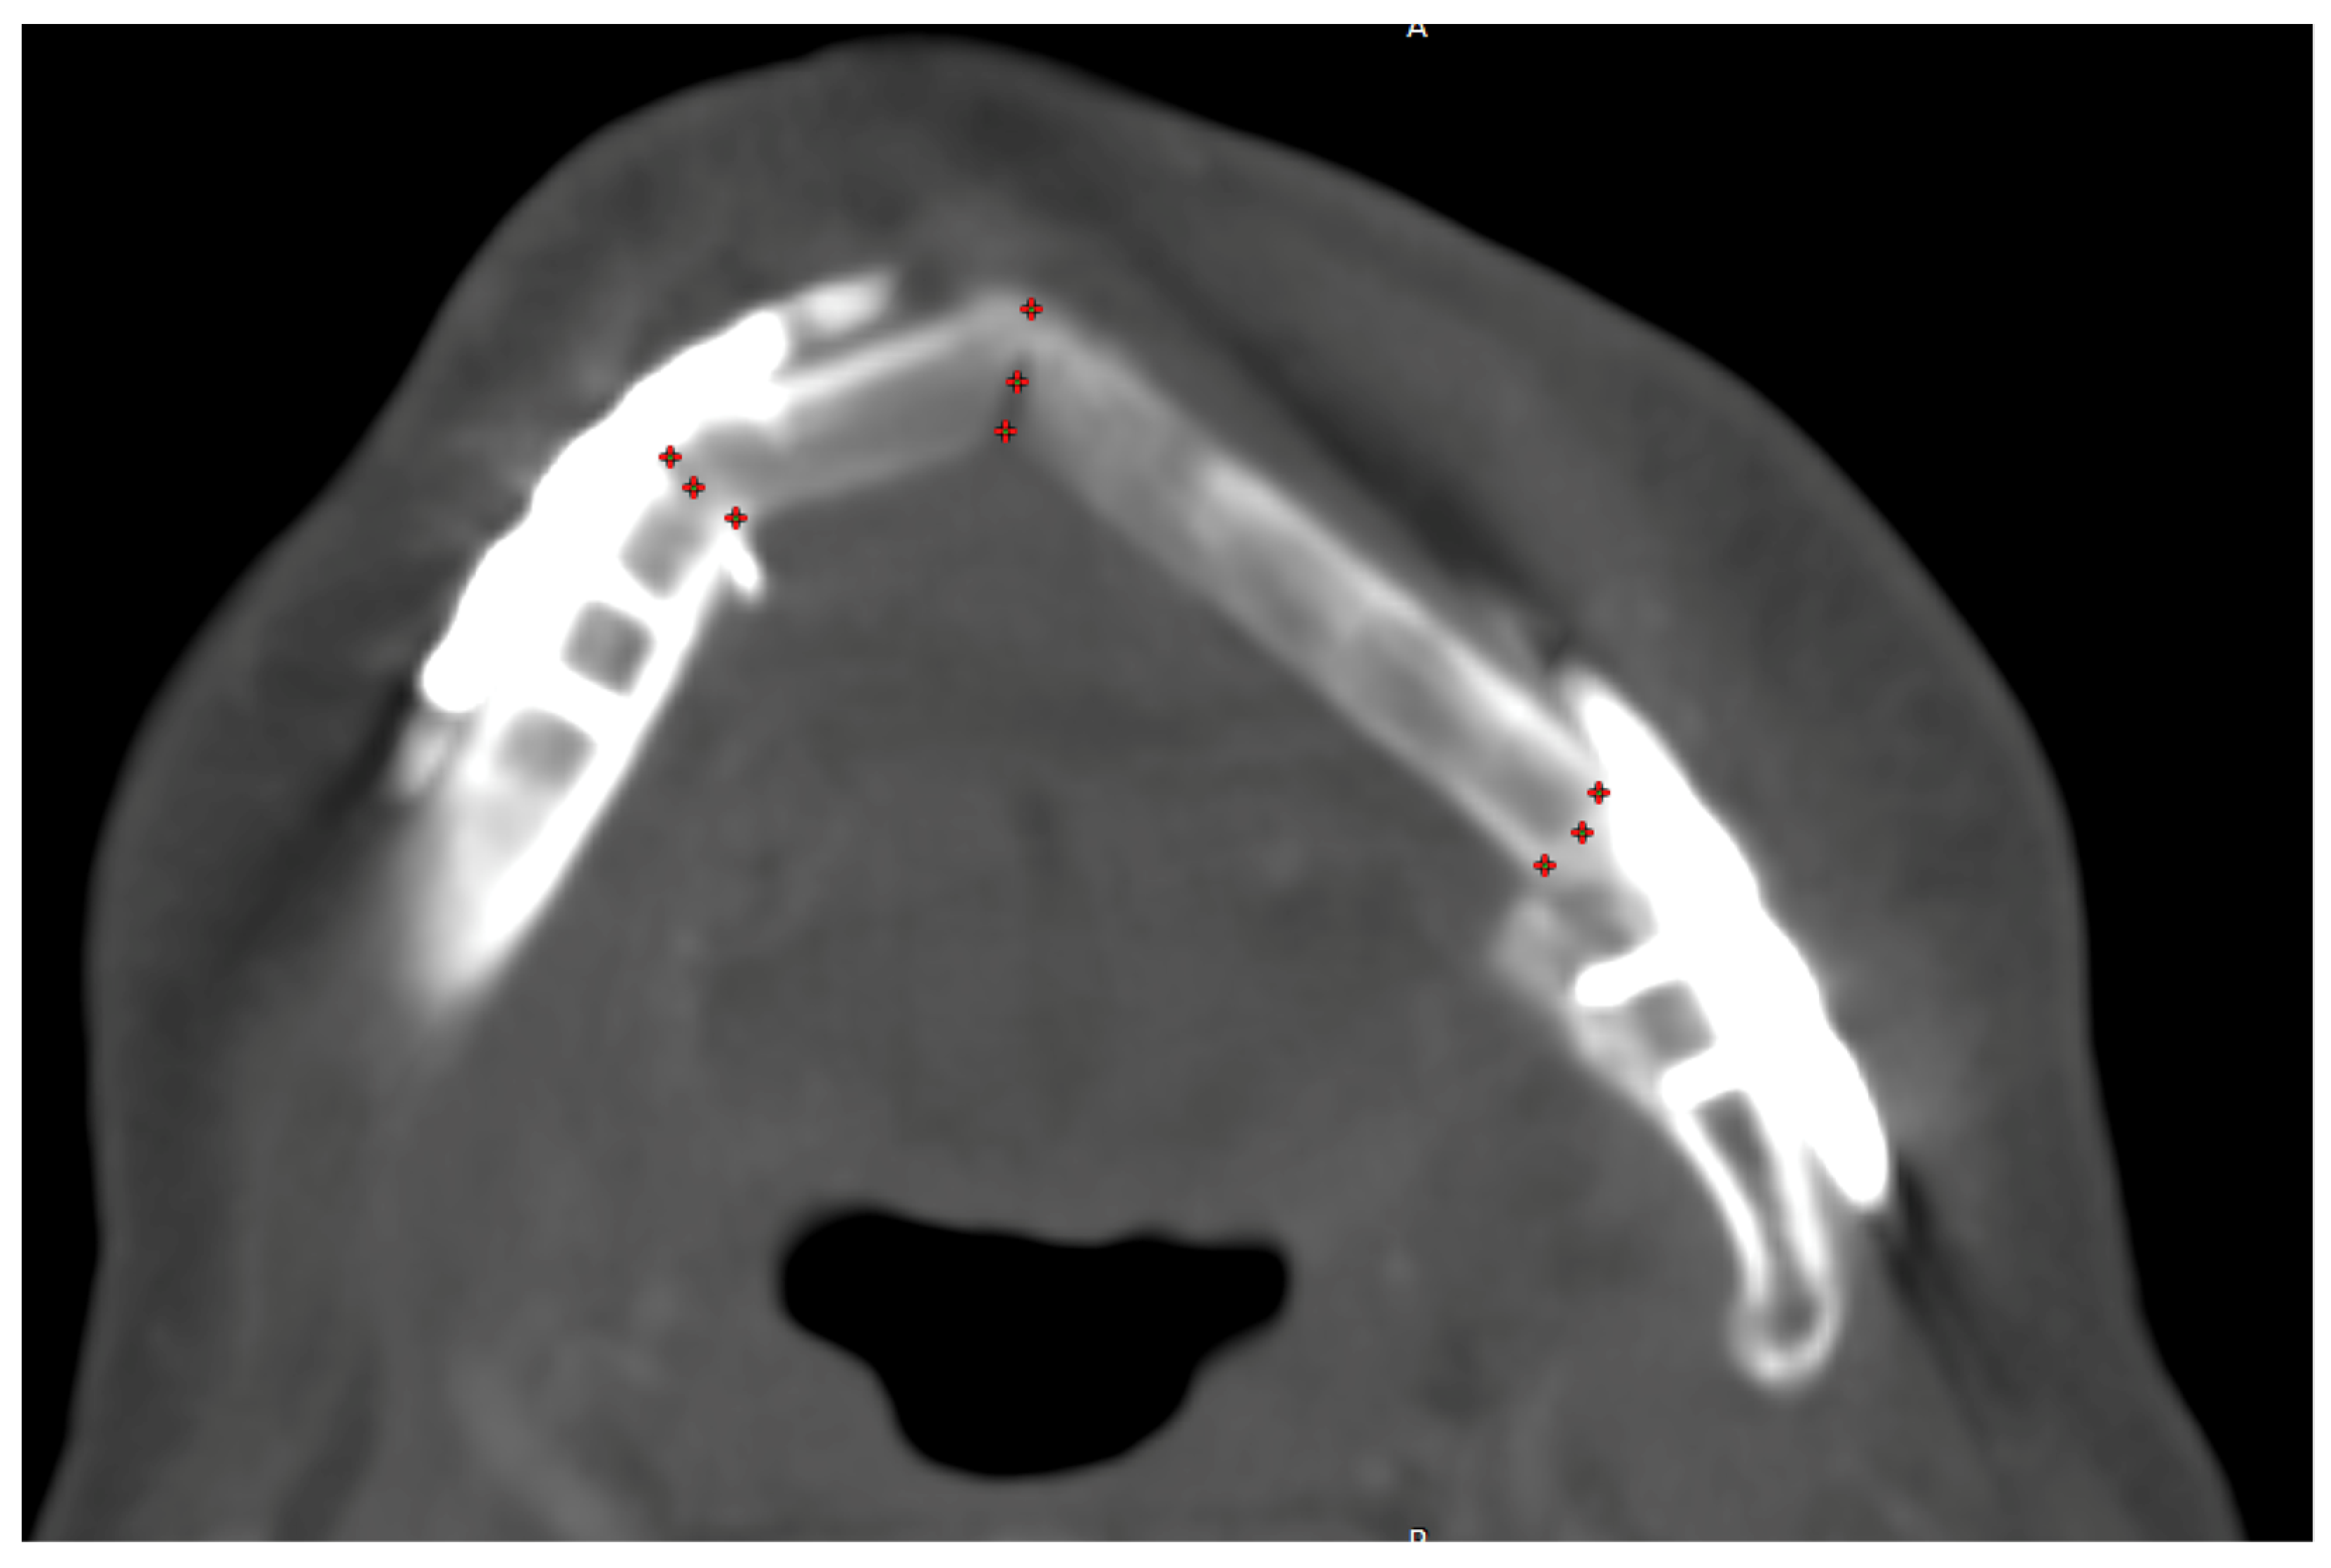

2.2. Radiographic Data Management

All available post-reconstructive CT scans were examined. For staging and follow-up, the radiological department of the university hospital Regensburg used mainly the CT-scanner Somatom Definition Flash (Siemens Healthineers AG, Forchheim, Germany) with standard neck protocol (reconstructed slice thickness 3.00 mm, increment 3.00 mm, kernel Br40) and Accupaque (GE Healthcare GmbH, Düsseldorf, Germany) as weight-adapted contrast media agents (1 mL CM/kg; contrast medium bolus followed by 30 mL NaCl flush; CM delay correlates with CM dose (dose in mL corresponds to delay in sec plus 10 s)). No additional postprocessing techniques for a reduction in beam-hardening artifacts were used. First of all, the CT scan was uploaded to the universal radiological software RadiAnt DICOM Viewer 2023.1 (Medixant, Poznan, Poland). The scan was centered and positioned for measurement in all three layers. In every point of contact, nine regions of interest (ROI of 0.01589 mm2) of Hounsfield Units (HU) were quantified in the axial plane (Figure 2), and the mean value of HU was gathered. Three contact points were chosen on each crestal, center, and basal level of the reconstructed mandible (vestibular, middle, and lingual) (Figure 3). After first evaluation, HU values in the middle of the center of the contact point were excluded due to the hollow inside of the fibula bone (Figure 2c; ROI blue #).

Measurement of Hounsfield Units in the CT scans: measurement of HU in the gap of all contact points with three ROIs each.

Moreover, the overlapping surface between bone segments, the transplanted bone graft, and the original mandible were quantified in square centimeters (cm2) by measuring a second ROI in the sagittal contact plane.

All HU measurements were repeated for every follow-up CT scan (Figure 4).